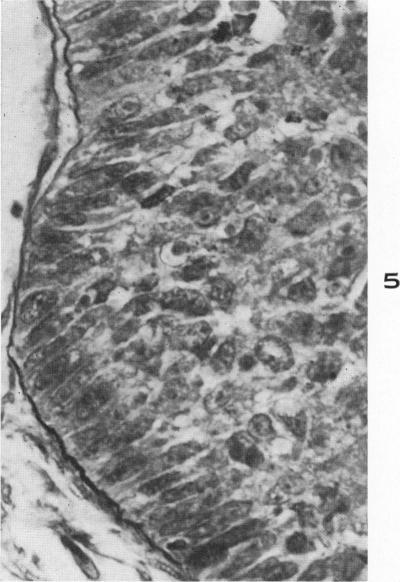

Muco-epidermoid tumors of the bronchus arising from surface epithelium.

Am J Pathol. 1958 Jul-Aug;34(4):671-83.